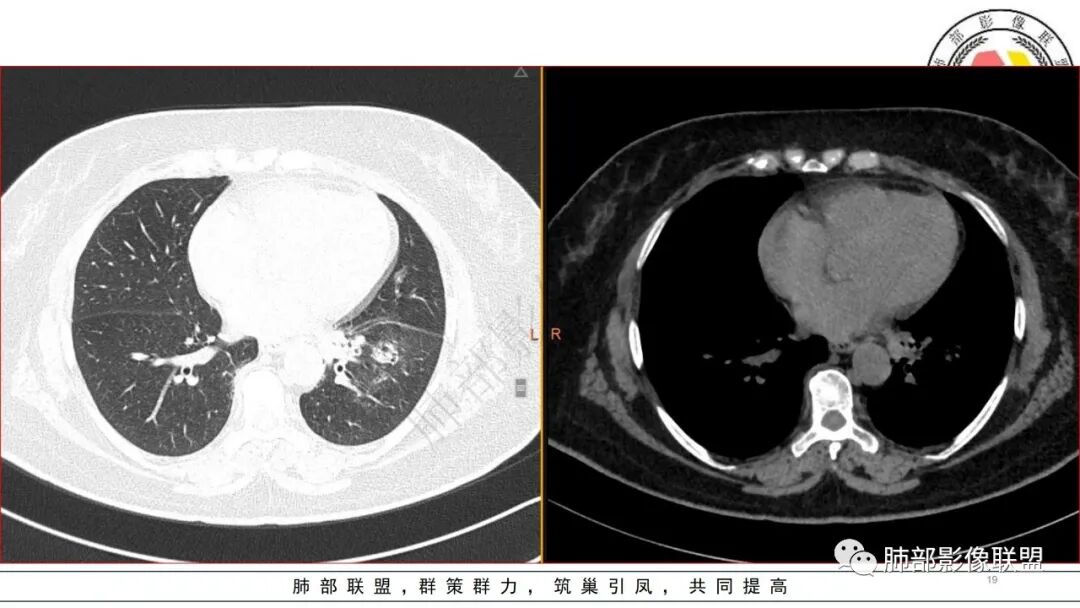

糖尿病基础,左下肺感染性病变,进展快,先是左肺大片实变,短时间复查出现空洞,治疗两周周边有吸收好转,空洞壁变薄。金毛结克,我倾向金葡菌。鉴别肺克。

老年患者,糖尿病病史14年,不规律降糖治疗,血糖控制不佳,咳嗽、喘息两天就诊,查血常规白细胞轻度升高,CRP显著升高,首诊CT提示左下基底大片实变,边界不清,周围播散灶,短期复查病灶呈吸收好转趋势,并出现多发空洞,空洞形态不规则,病灶内未见气液平,考虑感染性病变:

老年女性,有14年糖尿病史,咳嗽、喘息2天。白细胞计数稍升高。1.13CT:左下肺大片实变,经抗感染治疗,短期变为多发气囊及空洞样病灶。病灶考虑气道来源,短期变化大,不支持肺结核诊断;无咯血症状,短时间内变化大,毛霉可能性小;肺克及金葡感染难以鉴别,建议完善降钙素原检查进一步判断。个人倾向于肺克。

短期内变化明显,左下肺随治疗进展可见气囊影,实变内可见空洞及支扩,考虑炎性感染性病变,病史较短,变化较大,可排除丅B及奴卡,无咳血可排除毛霉,综和考虑金葡>肺克,其次要考虑合并铜绿感染的可能

3.五天后及十三天后病灶变化明显,实性密度影吸收缩小,边界趋于清楚,显示多空腔。

3.金黄色葡萄球菌临床中毒症状明显,常寒颤高热起病,血源性感染者常有皮肤脓肿、伤口感染、蜂窝织炎、化脓性骨髓炎等等。病情变化快,影像进展迅速,短期内(如一两天内)迅速出现的有张力的菲薄气囊影,或多发成串分布的,尤具特征性!较之其他感染,短期内易出现脓胸。本例上述特征似乎不明显。

4.肺炎克雷伯杆菌肺炎病灶也易形成脓腔。本例患者未出现典型金葡感染影像学特征,患者临床表现相对“逍遥”缓慢,结合实验室检查,更符合肺炎克雷伯杆菌肺炎。